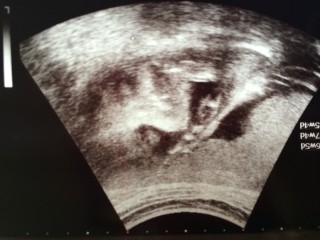

スクリーニング検査の時の一枚

検査の時は、ずっと激しく動き回って

検査が困難だったみたい(^◇^;)

検査が終わる頃、撮ってくれたんだけど

あくびをして寝始める時一枚だったの

めっちゃかわゆーい

体重おおよそ870-950グラムほど!

男の子です♡

通常より少し大きめと言われました。

すくすく成長してね~